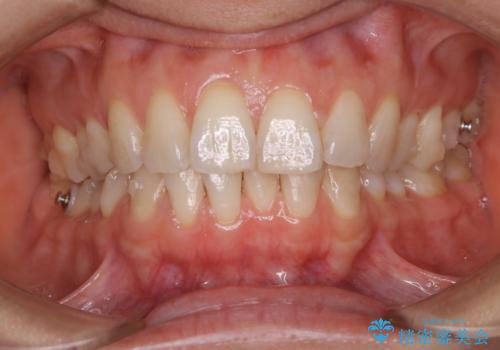

上下の真ん中を合わせて横顔シルエットも改善

インビザラインFULLで奥歯の噛み合わせから改善させることで、上下の真ん中位置をしっかり合わせることが出来ました。

横顔のシルエットも改善させることができ、大変喜んでいただけました。